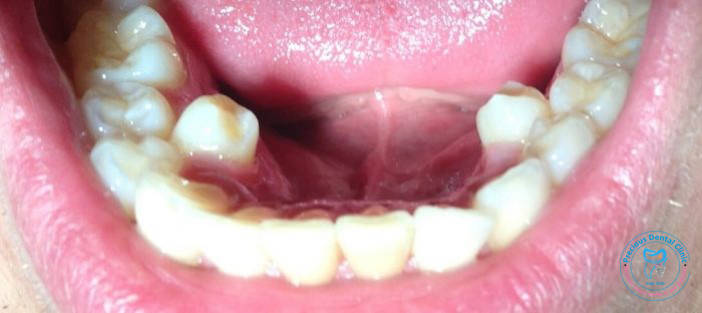

Collection of photos, here you will find the photos of doctor, services, environment and work.